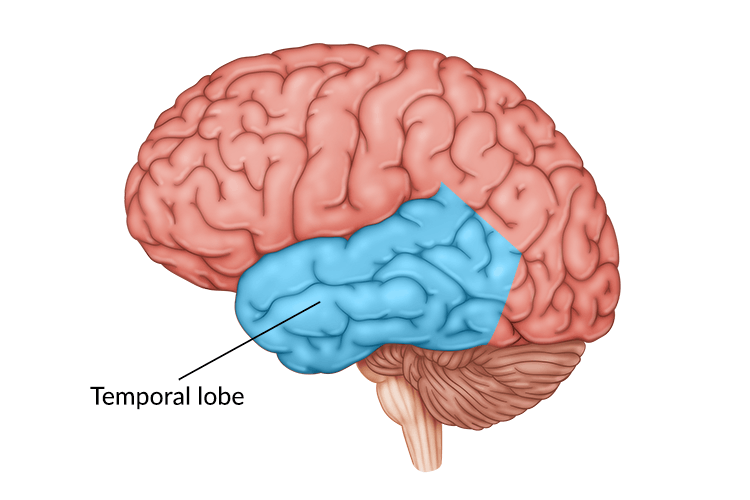

Temporal Lobe Anatomy Location Function Damage Epilepsy

https://healthjade.com/wp-content/uploads/2019/05/temporal_lobe.jpg

Location Of Temporal Lobe Mayo Clinic

https://www.mayoclinic.org/-/media/kcms/gbs/patient-consumer/images/2013/08/26/10/11/my00133_im00316_bn7_temporalthu_jpg.ashx

Temporal Lobe SpinalCord

https://www.spinalcord.com/hs-fs/hubfs/The%20brain%20-%20temporal%20lobe.jpg?width=726&name=The%20brain%20-%20temporal%20lobe.jpg

Temporal Lobe The Definitive Guide Biology Dictionary

Temporal Lobe Function Location And Structure

Temporal Lobe

Temporal Lobe What Is It Location Structure Functions Injuries

Temporal Lobe What Is It Location Structure Functions Injuries